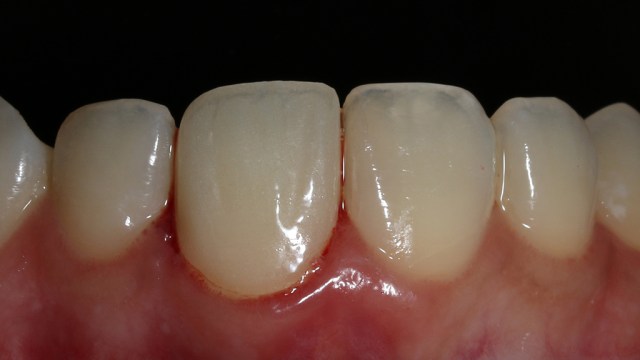

Foto klinis setelah pemasangan crown

Alhamdulillah pasien nya senang sekali…. dia puas dan saya pun senang karena dapat memenuhi keinginan pasien…..

Begini hasil akhir setelah sementasi crown…